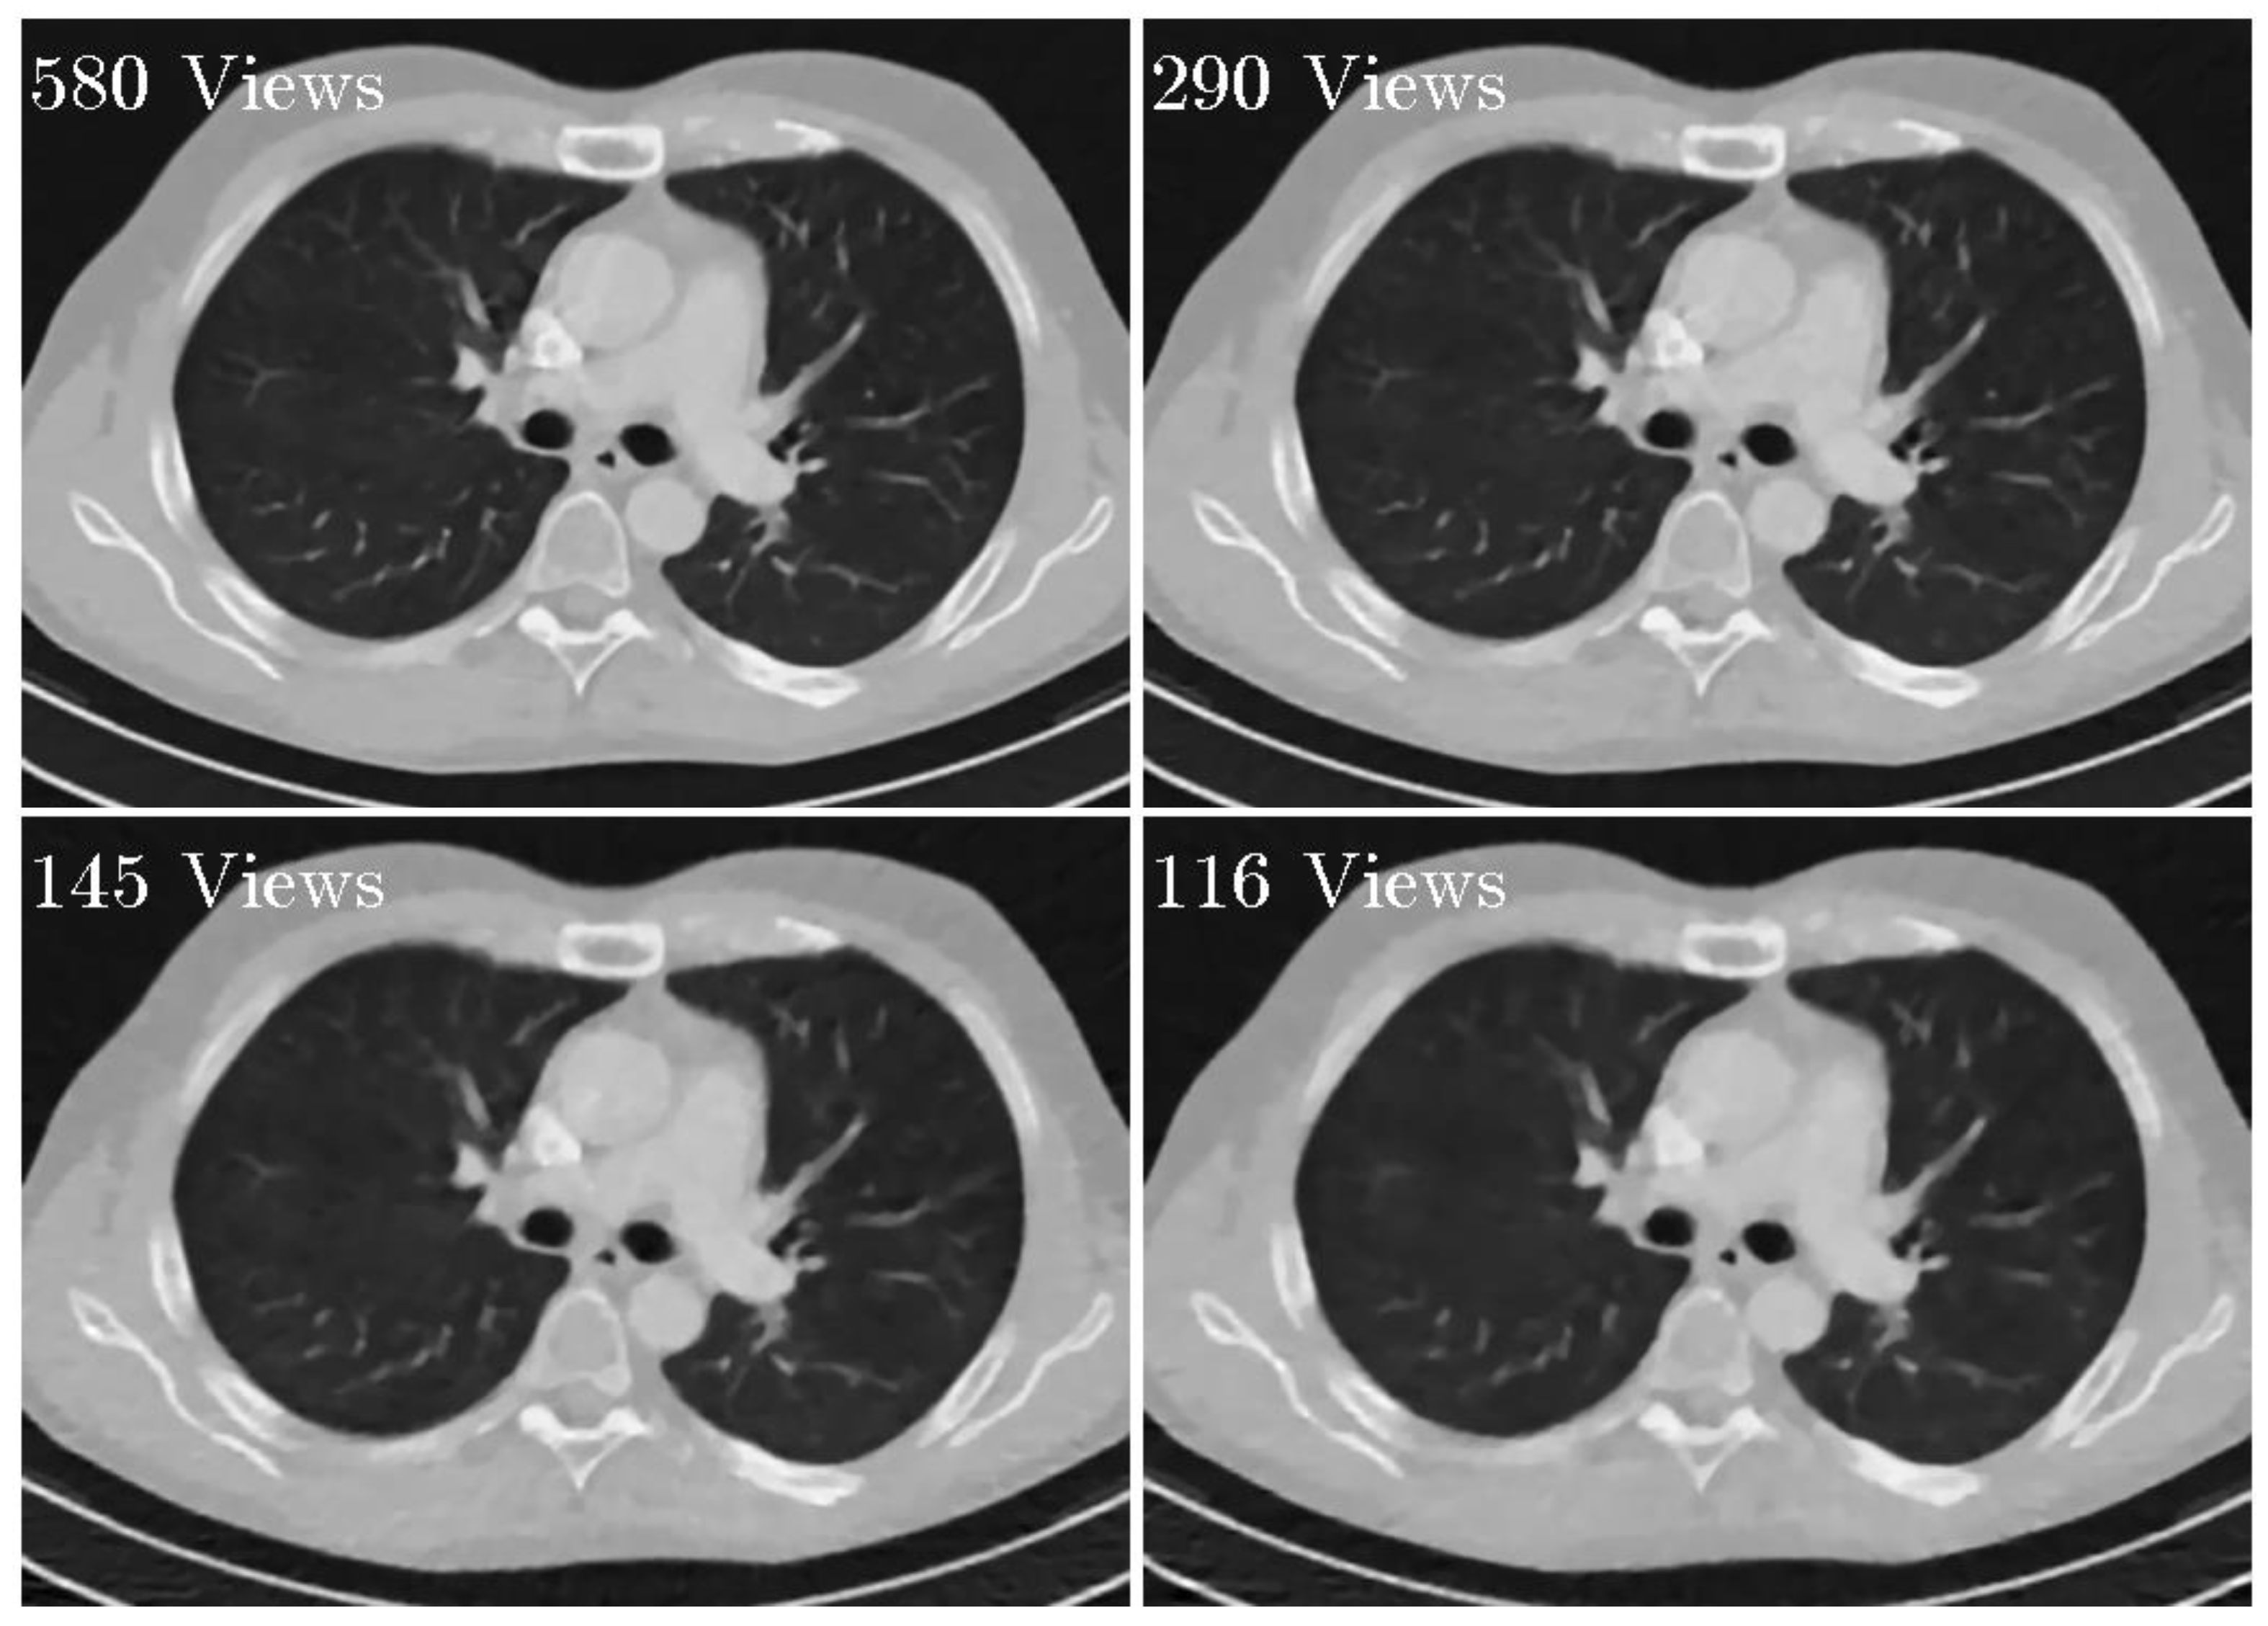

To evaluate the impact of the number of projections, simulated experiments with 580, 290, 145, and 116 views were performed. For all experiments, σ were set to 0.5, L K were set to be 3. When the number of projection view decreases, the regularization parameter λ should be increased accordingly to obtain high quality reconstructed results. For the reconstructions from 580, 290, 145, and 116 views, λ were set to 3 × 10−6, 4 × 10−6, 6 × 10−6, and 8 × 10−6, the number of subset were set to 20, 10, 5, and 4, respectively. The reconstruction results are shown in Figure 9. It can be observed that our proposed method can suppress the noise effectively. In the case of 580 views, the reconstruction result was almost as good as that reconstructed from 1160 views in Figure 4c. In the cases of 290, 145, and 116 views, our proposed method still obtains high quality reconstruction results.

Figure 9. Reconstructed images using the SIR-STV1 method with respect to different views. The display window is [−1000, 667] HU.